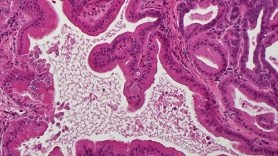

RNF43 mutations accelerate KRAS-driven pancreatic cancer, stimulate immune microenvironment remodeling

Roughly 5-10% of all pancreatic cancers have loss-of-function mutations in the ring finger protein 43 (RNF43) gene, and this is one of the most commonly mutated genes in pancreatic pre-cancerous cysts. Unfortunately, no effective targeted therapies are available to treat patients with RNF43 mutations. Using a genetically engineered mouse model, researchers led by Abdel Nasser Hosein, M.D., Sonja Woermann, M.D., and Anirban Maitra, M.B.B.S., studied RNF43 in the context of mutant KRAS. They discovered that RNF43 acts as a tumor suppressor and its deletion cooperates with mutant KRAS to accelerate the development pre-cancerous lesions and pancreatic cancers. Additionally, RNF43 loss resulted in a distinct tumor immune microenvironment marked by increased numbers of anti-tumor lymphocytes and fewer suppressive myeloid cells, suggesting these tumors may be susceptible to immune checkpoint inhibitors. The immune signaling protein CXCL5 was decreased in RNF43-deficient tumors, pointing to a possible target to mediate the unique immune landscape in these cancers. Learn more in Gastroenterology

Intraductal papillary mucinous neoplasms develop in a laboratory model with mutant KRAS and loss of Rnf43 function. These pancreatic cystic lesions are bona fide precursors to pancreatic cancer, and the model offers new opportunities for treatment and interception. Image courtesy of the Anirban Maitra laboratory.